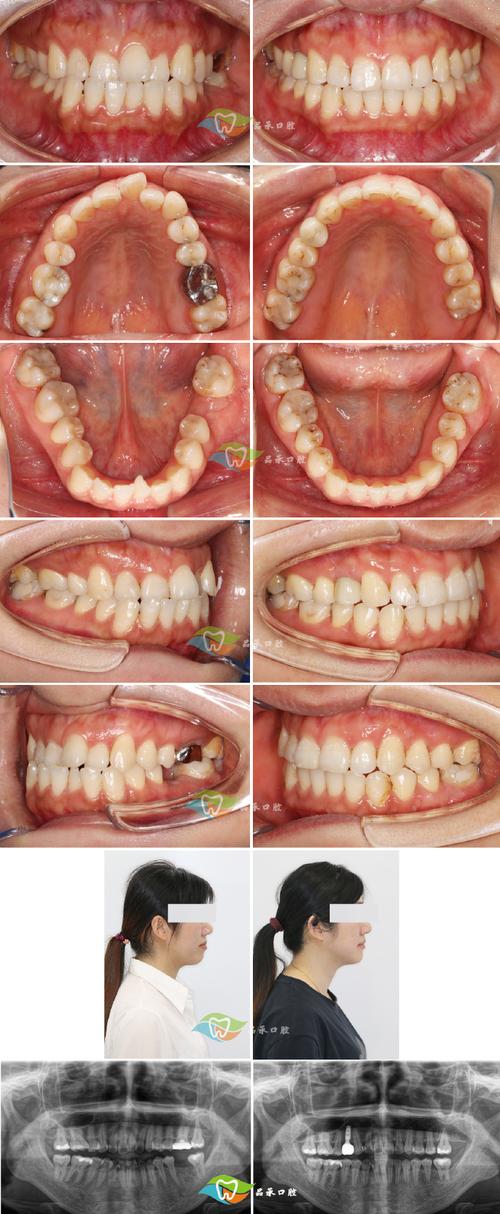

- 临床检查:观察牙齿排列、咬合关系、面部对称性(如下颌是否前突、面部中份是否凹陷),检查颞下颌关节及口腔黏膜健康状况。

- 影像学检查:拍摄全景片(观察全口牙根、牙槽骨及颌骨形态)、头颅侧位片(分析颌骨大小、位置关系及面部软组织轮廓)、CBCT(三维评估骨量及牙根位置,复杂病例必备)。

- 模型分析:取制牙齿石膏模型,测量牙齿拥挤度、Spee曲线深度等数据,辅助设计牙齿移动方案。